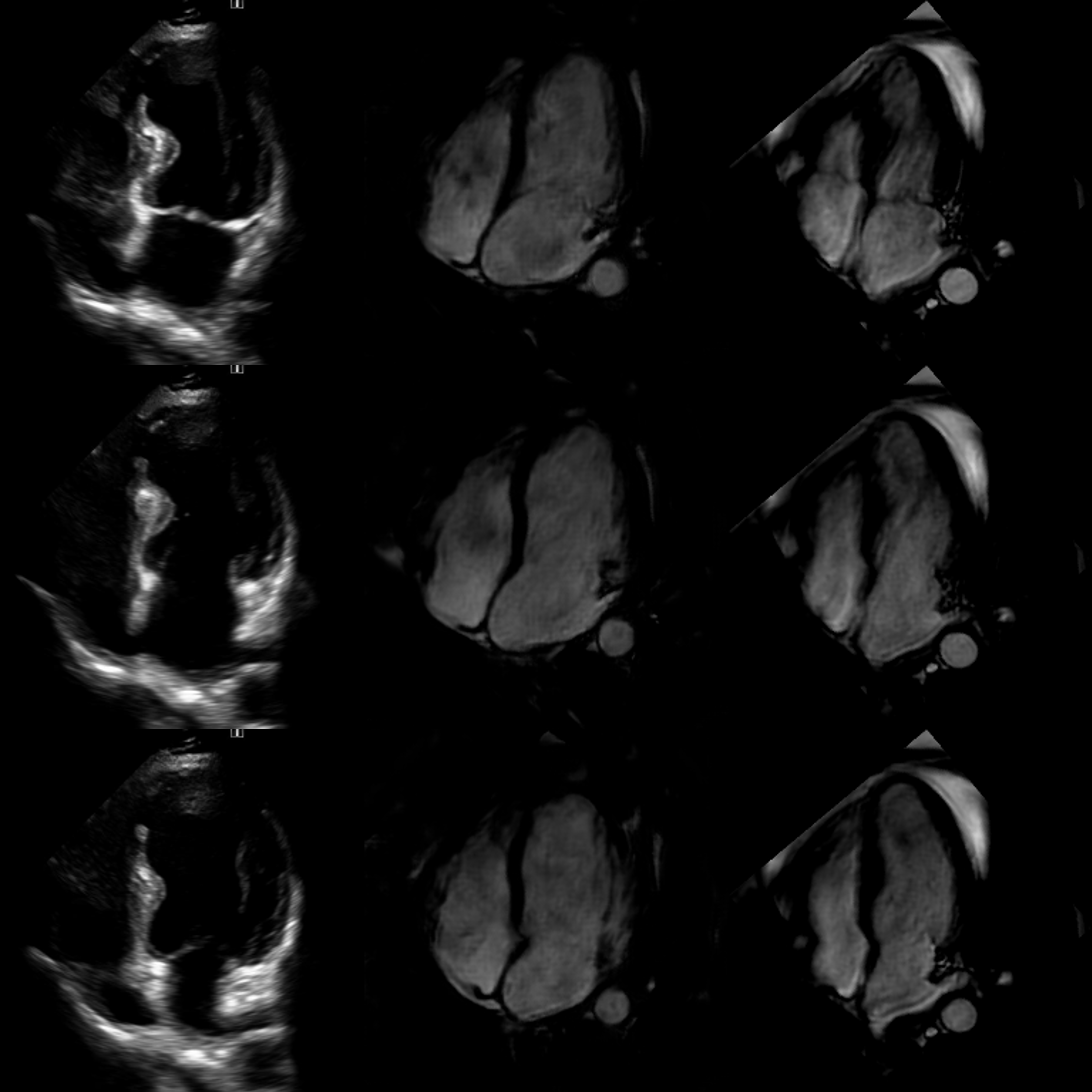

Refer to captionABC

Figure 11: Patient 2: Comparison of echocardiography (Column A), synthetic cardiac MRI (Column B), and real cardiac MRI (Column C) images. Echocardiography images show 3 different phases of one heartbeat, with corresponding synthetic and real cardiac MRI views.

Figure 12: Patient 9: Comparison of echocardiography (Column A), synthetic cardiac MRI (Column B), and real cardiac MRI (Column C) images. Echocardiography images show 3 different phases of one heartbeat, with corresponding synthetic and real cardiac MRI views.